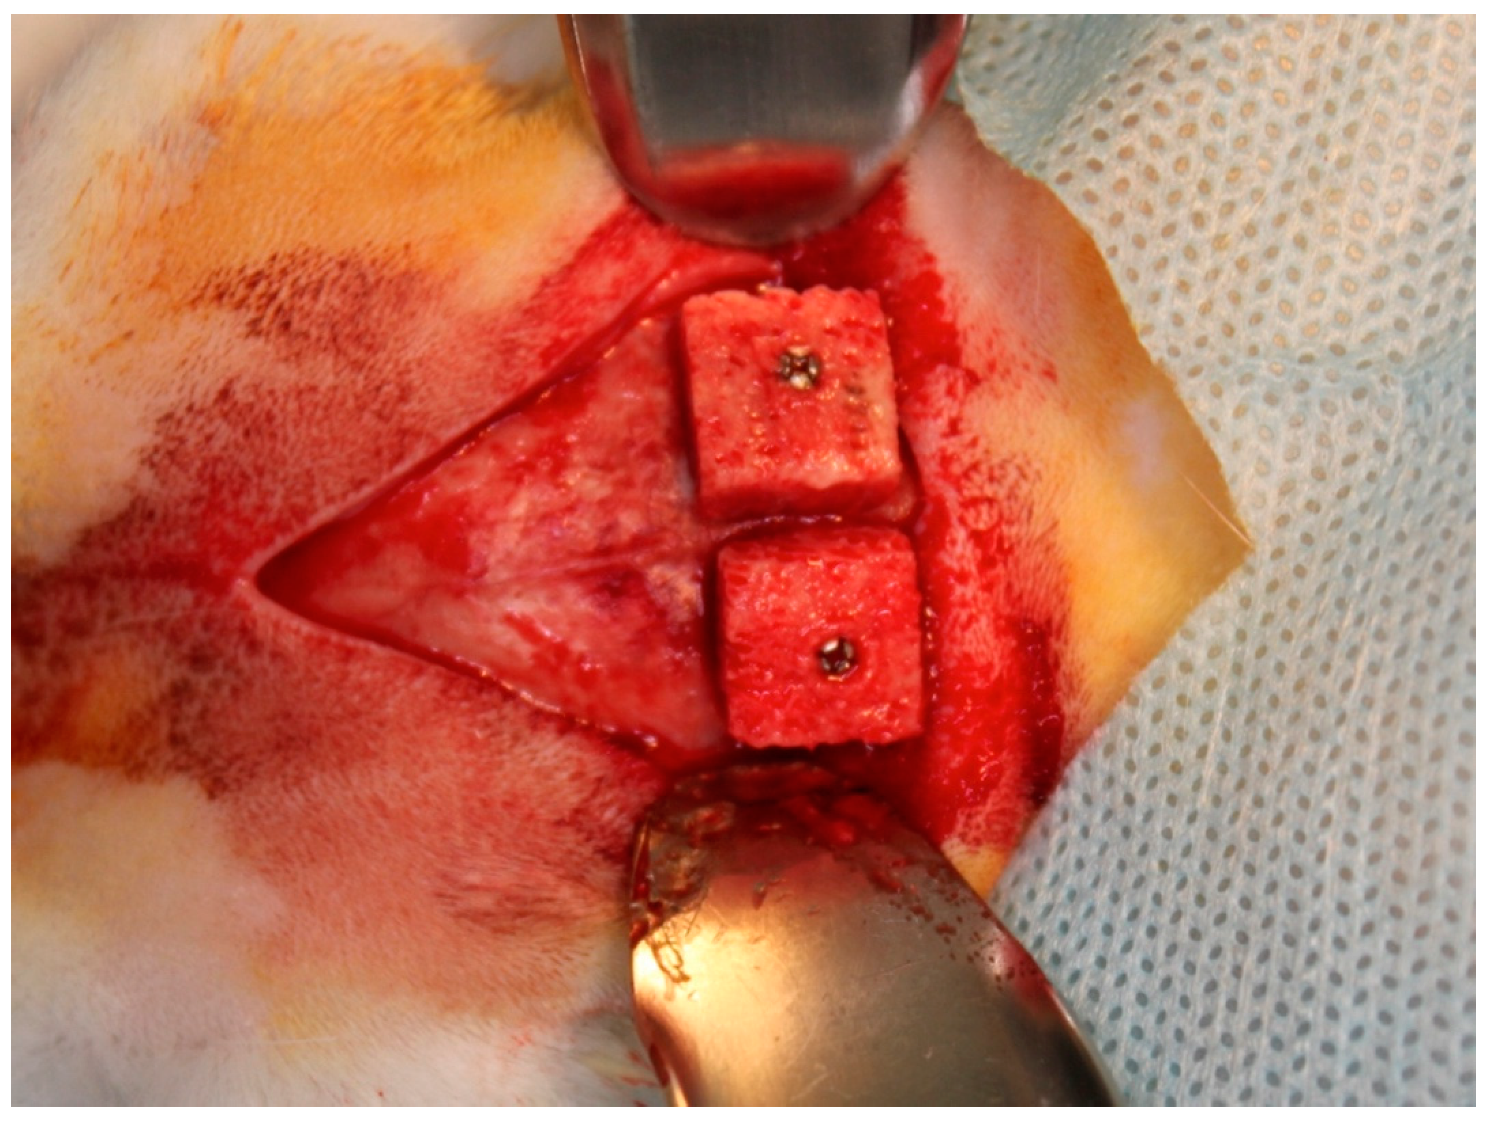

2.9. Experimental Design and Surgical Protocol

2.10. Histological Preparation and Histomorphometric Evaluation